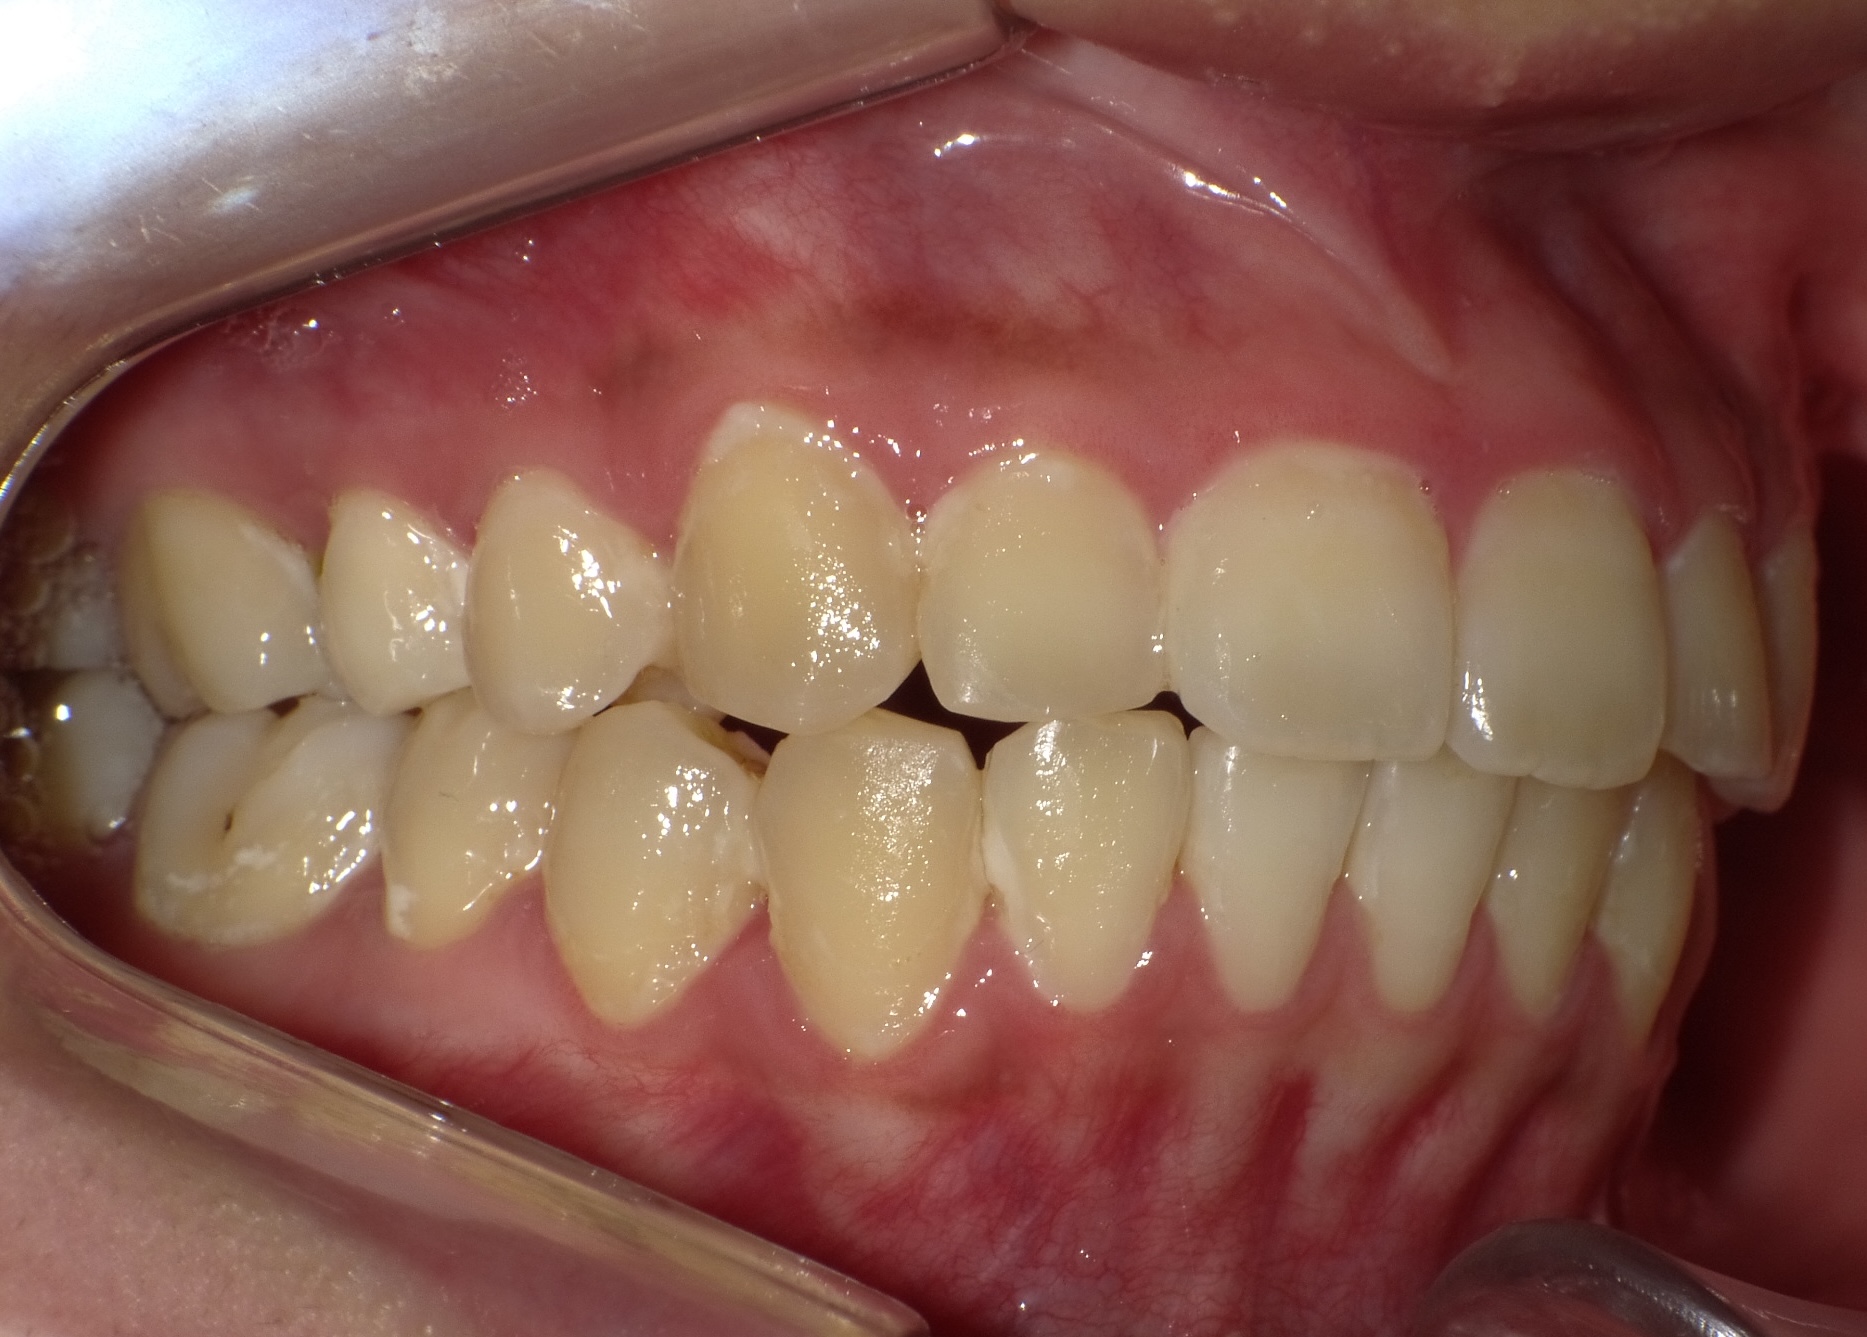

症例1-③

そこで当院では、ここからは、当院の成人非抜歯の技術を用いて、永久歯を抜くことなく(親知らずは除く)治療をゴールまでもって行きます。

症例1-③の写真が完成時の所見です。いかがでしょう、口もとも美しくきれいな永久歯列の完成です。